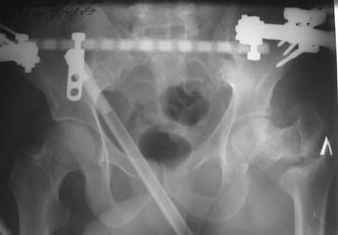

Я думаю в данном случае для начала необходимо наложить спице - стержневой аппарат таз - бедро с низведением проксимального отломка. Во-вторых открытый остеосинтез DHS c костной аутопластикой. Доступ чрезъягодичный. В даанном случае возможны большие трудности при введения gamma.

Возможно, пример (в приложении) поможет Вам определиться с выбором тактики лечения (у нашего пациента, кроме тугого ложного сустава вертельной области, сложная деформация н/3 бедренной кости; т.к. это не имеет значения к обсуждаемой теме - оставил "за кадром"). Как Вы видите, мы в данном случае не вводили чрескостные элементы в зону установки имплантата. При отказе от наложения опоры на таз (кстати, она не обязательно может быть громоздкая спицевая; арки со стержнями-шурупами, введенными в крыло подвздошной вполне достаточно) "не удивляйтесь", если опора со стержнями-шурупами, введенными в вертельной области в скором времени дестабилизируется, возникнет воспаление мягких тканей у чрескостных элементов. Такая опора "имеет на это право": нагрузка конечности от вершины дистального фрагмента до кончиков пальцев ляжет на нее. А двух-трех введенных рядом стержней-шурупов, как их не разноси от фронтальной плоскости, в данном

случае явно недостаточно для адекватной фиксации. + для того, чтобы выбрать оптимальные чрескостные элементы для промежуточной и дистальной опор, можете воспользоваться атласом

В приложении пример пациента, близкого по картине к тому, что представил Виктор (варус и смещение периферического отломка на поперечник кзади). Сделали как раз то, что Виктор исходно намеревался - аппаратная коррекция и затем гамма.